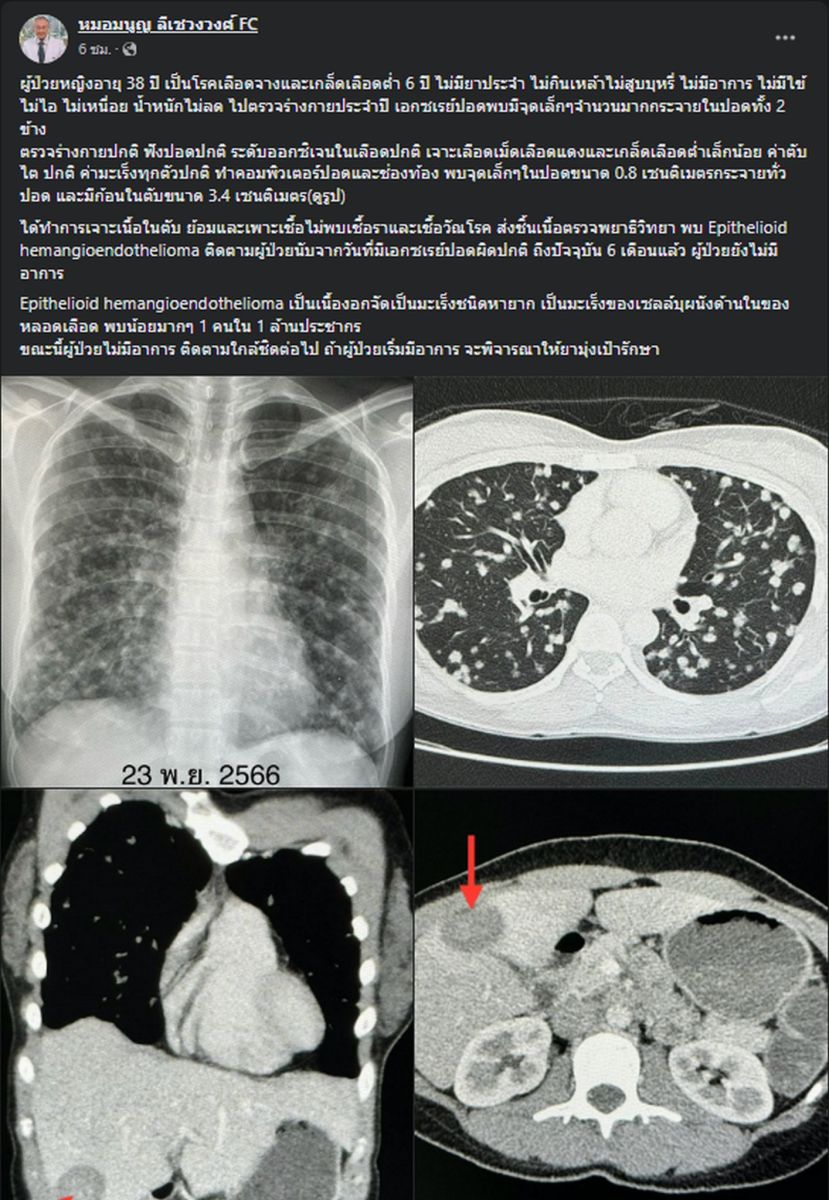

15 กุมภาพันธ์ 2567 นพ.มนูญ ลีเชวงวงศ์ แพทย์เฉพาะทางด้านโรคระบบการหายใจ โรงพยาบาลวิชัยยุทธ โพสต์เฟซบุ๊กรูปภาพฟิล์มเอกซเรย์ พร้อมระบุข้อความว่า ผู้ป่วยหญิงอายุ 38 ปี เป็นโรคเลือดจางและเกล็ดเลือดต่ำ 6 ปี ไม่มียาประจำ ไม่กินเหล้าไม่สูบบุหรี่ ไม่มีอาการ ไม่มีไข้ ไม่ไอ ไม่เหนื่อย น้ำหนักไม่ลด ไปตรวจร่างกายประจำปี เอกซเรย์ปอดพบมีจุดเล็กๆ จำนวนมากกระจายในปอดทั้ง 2 ข้าง

ตรวจร่างกายปกติ ฟังปอดปกติ ระดับออกซิเจนในเลือดปกติ เจาะเลือดเม็ดเลือดแดงและเกล็ดเลือดต่ำเล็กน้อย ค่าตับไต ปกติ ค่ามะเร็งทุกตัวปกติ ทำคอมพิวเตอร์ปอดและช่องท้อง พบจุดเล็กๆ ในปอดขนาด 0.8 เซนติเมตรกระจายทั่วปอด และมีก้อนในตับขนาด 3.4 เซนติเมตร ได้ทำการเจาะเนื้อในตับ ย้อมและเพาะเชื้อ ไม่พบเชื้อราและเชื้อวัณโรค ส่งชิ้นเนื้อตรวจพยาธิวิทยา พบ Epithelioid hemangioendothelioma ติดตามผู้ป่วยนับจากวันที่มีเอกซเรย์ปอดผิดปกติ ถึงปัจจุบัน 6 เดือนแล้ว ผู้ป่วยยังไม่มีอาการ

Epithelioid hemangioendothelioma เป็นเนื้องอก จัดเป็นมะเร็งชนิดหายาก เป็นมะเร็งของเซลล์บุผนังด้านในของหลอดเลือด พบน้อยมากๆ 1 คนใน 1 ล้านประชากร

นพ.มนูญ ระบุ อีกว่า "ขณะนี้ผู้ป่วยไม่มีอาการ ติดตามใกล้ชิดต่อไป ถ้าผู้ป่วยเริ่มมีอาการ จะพิจารณาให้ยามุ่งเป้ารักษา"